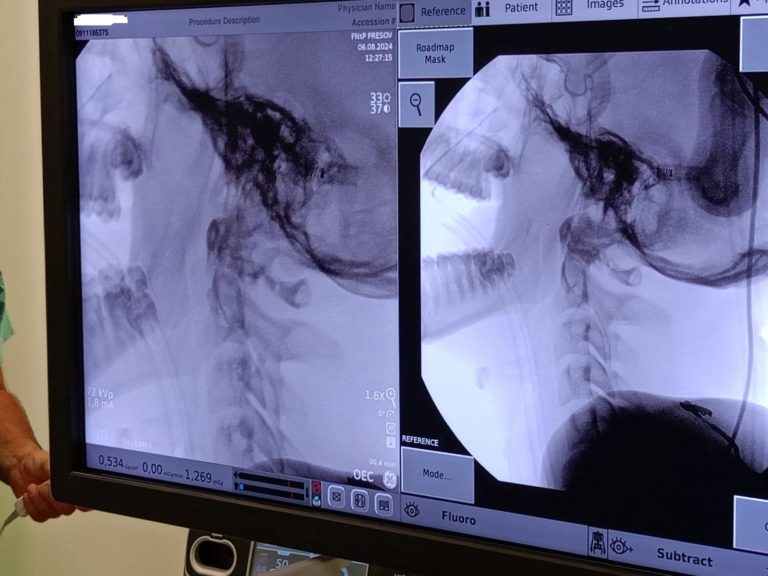

„Išlo o zlomeninu zuba čapovca – dens axis. Práve pre túto diagnózu sme vyhodnotili ako vhodnú použiť metódu jeho podpory biovstrebateľnou skrutkou. Podarilo sa nám to bez komplikácií, pacient je v stabilizovanom stave, predpokladáme bezproblémový priebeh rekonvalescencie,“ priblížil zástupca primára oddelenia úrazovej chirurgie nemocnice v Prešove Patrik Mikluš.

Biovstrebateľné implantáty sa na Slovenku používajú od roku 2017. Sú to tzv. pod röntgenom neviditeľné implantáty, ktoré sú vlastnosťami podobné ľudskej kosti a zmiznú bez ďalšej operácie, vynikajúco sa správajú v tele pacienta. Implantáty sú umiestnené vo vnútri kostí. Vzhľadom na povahu materiálu odpadávajú alergické reakcie a dochádza k vstrebávaniu materiálu bez vplyvu na ľudský a hlavne detský organizmus.